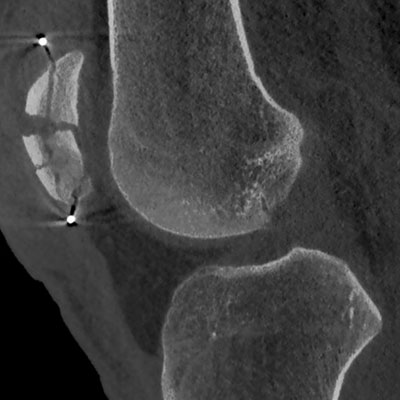

Mit unserem neuen CT-Gerät (CT steht für „Computertomographie“. Die Computertomographie ist ein bildgebendes Verfahren, das mithilfe von Röntgenstrahlen und Computertechnologie detaillierte Querschnittsbilder des Körpers erzeugt) der neuesten Generation leisten wir einen Quantensprung in der präzisen Untersuchung. Diese fortschrittliche Technologie liefert überlagerungsfreie Querschnittsbilder des Körpers und ermöglicht eine Visualisierung von Gewebsregionen, die mit herkömmlichen Röntgenuntersuchungen nicht erreichbar sind.

Besonders in Bereichen, in denen feinste Strukturen wie Blutgefäße, Lunge oder winzige Knochen beurteilt werden müssen, bietet die doppelt so hohe Bildschärfe dieses CT-Geräts signifikante Vorteile. Klare und präzise Diagnosen erhöhen die Sicherheit für die Patienten und erleichtern die Therapieentscheidungen. Die zusätzliche Nutzung der Energieinformation liefert umfassendere diagnostische Aussagen, wodurch auf zeit- und kostenintensive Zusatzuntersuchungen oft verzichtet werden kann.

Unser neues CT zeichnet sich durch eine deutlich reduzierte Strahlendosis und kürzere Untersuchungsdauer aus, dank der hohen Geschwindigkeit, mit der die Scanner in Sekundenbruchteilen 3-D-Schnittbilder erstellen. Dieses Niveau der Diagnostik setzt neue Maßstäbe in der Sportorthopädie im Professor Citak Gesundheitszentrum.